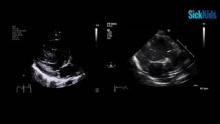

This is a term female newborn with a birth weight of 2.73 kg and diagnosis of VACTERL association, pulmonary atresia, ventricular septal defect (VSD), and malposed great vessels, who was a non-candidate for early complete repair. She was initially palliated with a 3.5x12 mm PDA stent at 6 days of age. Postoperative course after neonatal trachea-esophageal fistula repair was complicated by recurrent desaturations and failure to progress with feeds due to cardiorespiratory distress. Computed tomography showed origin muscular stenosis of bilateral pulmonary arteries (PA), with negligible flow in the left PA. The patient was electively taken to the operating room at 4 months of age for surgical palliation. Cardiopulmonary bypass with bicaval cannulation was initiated and the PDA was ligated. Distal PAs were controlled with Yasargil Clips and the main PA was incised. Protruding PDA stent and thickened tissues were excised from the PAs, followed by bilateral reconstruction using autologous pericardium. Next, the heart was arrested with anterograde cardioplegia. A 6 mm Gore-Tex RVPAC was anastomosed from the right infundibular ventriculotomy site to the central PA with double-layer sutures at the proximal anastomosis. Post-repair SpO2 was 88%.